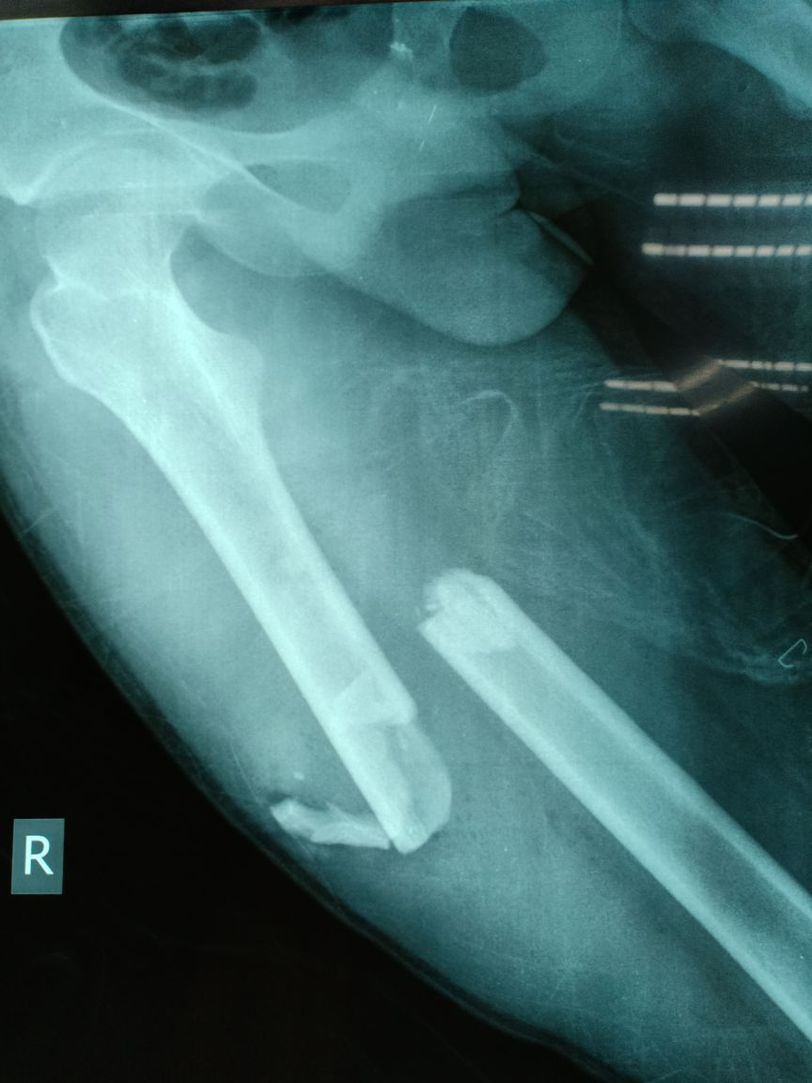

Open femur fracture,24y male got MVA , he directed to emergency operation